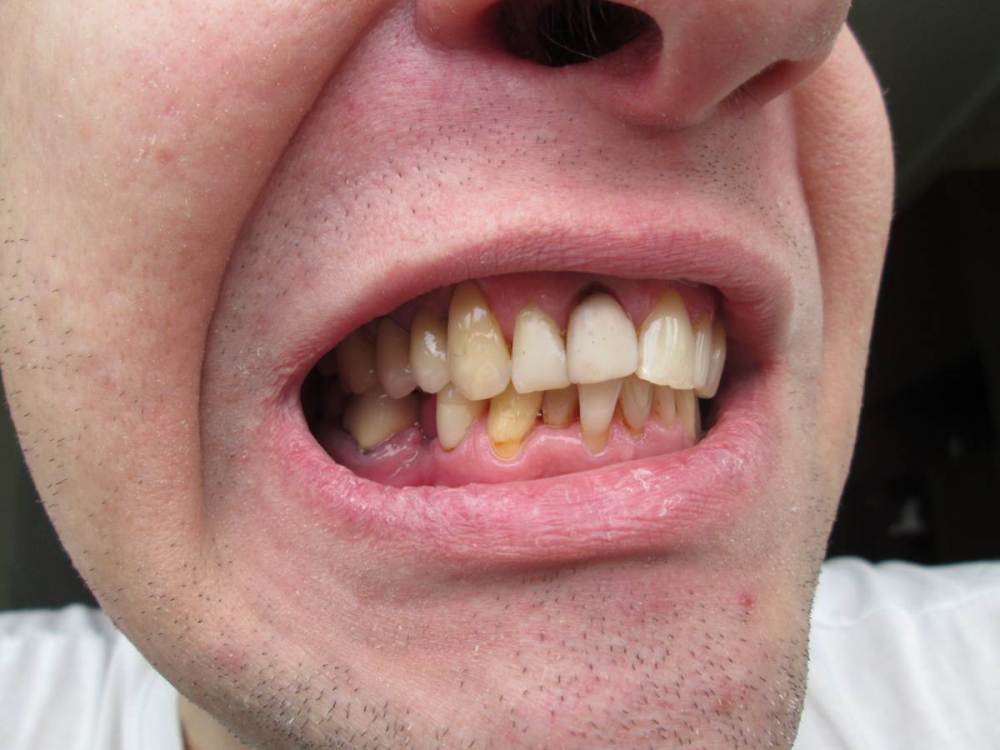

Jonik Опубликовано 24 апреля, 2022 Поделиться Опубликовано 24 апреля, 2022 Здравствуйте! У меня клиновидный дефект, убыль костной ткани и рецессии десны. Было несколько консультаций у ортодонтов, мнения разные: 1) Брекеты ставить нельзя, недостаточно костной ткани, брекеты усугубят ситуацию; 2) Брекеты можно поставить, но результат непредсказуем, можно потерять зубы (передние нижние); 3) Брекеты поставить можно и нужно или будет хуже. Прошу вашего совета как поступить, у меня два вопроса: 1) Нужны ли мне брекеты, помогут ли они в моем случае; 2) Можно ли установить мне брекеты, учитывая объем кости и тд. Есть КТ по ссылке https://drive.google.com/drive/folders/1zs22D5kDglz_UOtPfKQ2lUmh8P5N8cv7?usp=sharing Ссылка на комментарий